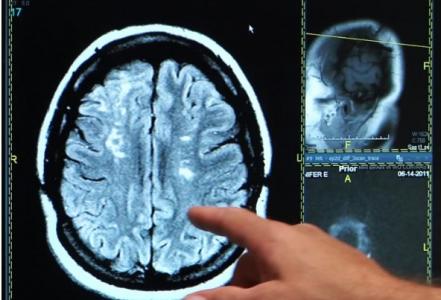

AVC : Une thérapie vertébrale expérimentale stimule la récupération

Cette intervention développée à l'Université de l'Alberta (Canada) basée sur une injection dans la colonne vertébrale se révèle efficace à restaurer les connexions entre le cerveau et la moelle épinière et à améliorer la récupération post-AVC. La preuve de concept apportée ici chez l’animal nécessitera de nombreuses recherches de confirmation et devra être encore testée chez l’Homme mais pourrait un jour jouer un rôle clé dans l'amélioration du rétablissement des victimes d'accident vasculaire cérébral (AVC).

L'AVC est la cause la plus fréquente d'incapacité chez les adultes. Le parcours typique de récupération implique une thérapie de réadaptation intensive. Au cours des premières semaines suivant un AVC, les patients ressentent des améliorations au fur et à mesure que le cerveau se reconfigure, mais finissent par atteindre un maximum et retrouvent rarement leurs capacités de départ.